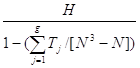

Полученный результат не является незначимым, поэтому нельзя считать, что выборки извлечены из одинаково распределенных совокупностей и что средние значения совокупностей совпадают. Но этот вывод является приближенным, так как в нашей таблице есть много совпадающих значений. Для учета влияния связей можно воспользоваться модифицированной формой статистики Краскела-Уоллиса [4]:

Н` =

, где g – число групп совпадающих значений, Тj = (t![]() - t

- t![]() ), t

), t![]() – число совпадающих наблюдений в

группе с номером j .

– число совпадающих наблюдений в

группе с номером j .